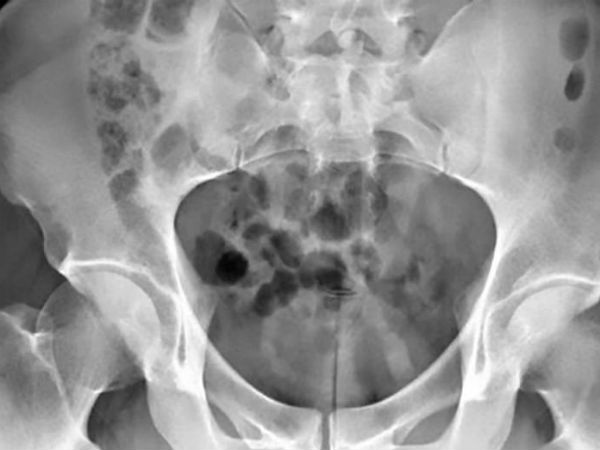

मिरर की रिपोर्ट के मुताबिक ताइवान के रहने वाले 30 साल के युवक ने सेक्स टॉय का लापरवाही से इस्तेमाल कर लिया। शख्स के ब्लैडर में करीब 20 सेंटीमीटर की प्लास्टिक रॉड जाकर फंस गई। शख्स डॉक्टर के पास जाने से बचता रहा। उसने दो दिनतक किसी को कुछ भी नहीं बताया, लेकिन उसकी ये गलती उसपर काफी भारी पड़ गई।

दो दिन तक युवक चुप रहा, लेकिन तीसरे दिन अचानक पेशाब के रास्ते से खून निकलने लगा, जिसके बाद वो डर गया। उसने फौरन अस्पताल पहुंचकर डॉक्टरों को पूरी बात बताई, जिसके बाद अस्पताल के यूरॉलजी डिपार्टमेंट के हेड जियान बैंग-बिंग की टीम ने ऑपरेशन तक युवक के ब्लैडर से सेक्स टॉय को निकाला और उसकी जान बचाई।

डॉक्टरों ने बताया कि सिस्टॉस्कपी प्रॉसेस के जरिए सेक्स टॉय को ब्लैडर से निकाला गया। प्लास्टिक रॉड की लंबाई 7.87 इंच और चौड़ाई 1 सेंटीमीटर थी। डॉक्टरों ने बताया कि युवक खुद को खुश करने के लिए इसका इस्तेमाल कर रहा था और उसकी लापरवाही के चलते वह ब्लैडर में फंस गया।